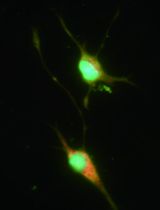

Purification and culture of endometrial epithelial cells (eEC) and stromal fibroblasts (eSF) from endometrial biopsies allows for downstream cell-specific in vitro studies. The utility of this protocol is the ease with which cells are purified without contamination from unwanted cell types, and the ability to use patient-paired eEC and eSF in experiments. These methods have been previously published, but here the protocol has been updated for maximum efficiency.